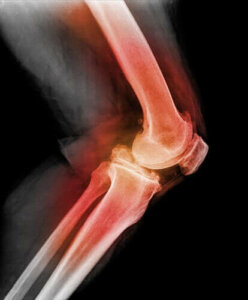

Щоб діагностувати вивих колінної чашечки, лікар торкнеться надколінка і зігне коліно, рухаючи ним в різні боки. За допомогою рентгенівського випромінювання, магнітно-резонансної томографії (МРТ) або комп’ютерної томографії (КТ), можна побачити вивих колінної чашечки та інші пошкодження коліна.